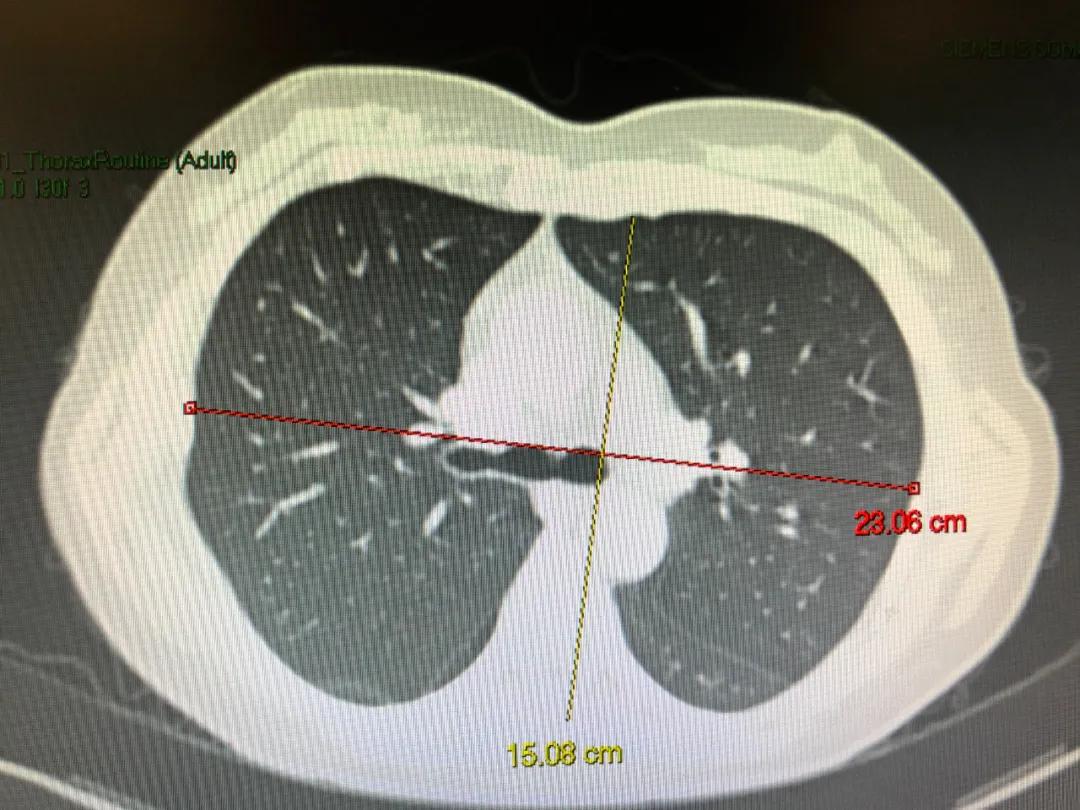

图为正常胸廓,其前后径15,横径23,基本比例为1:1.5